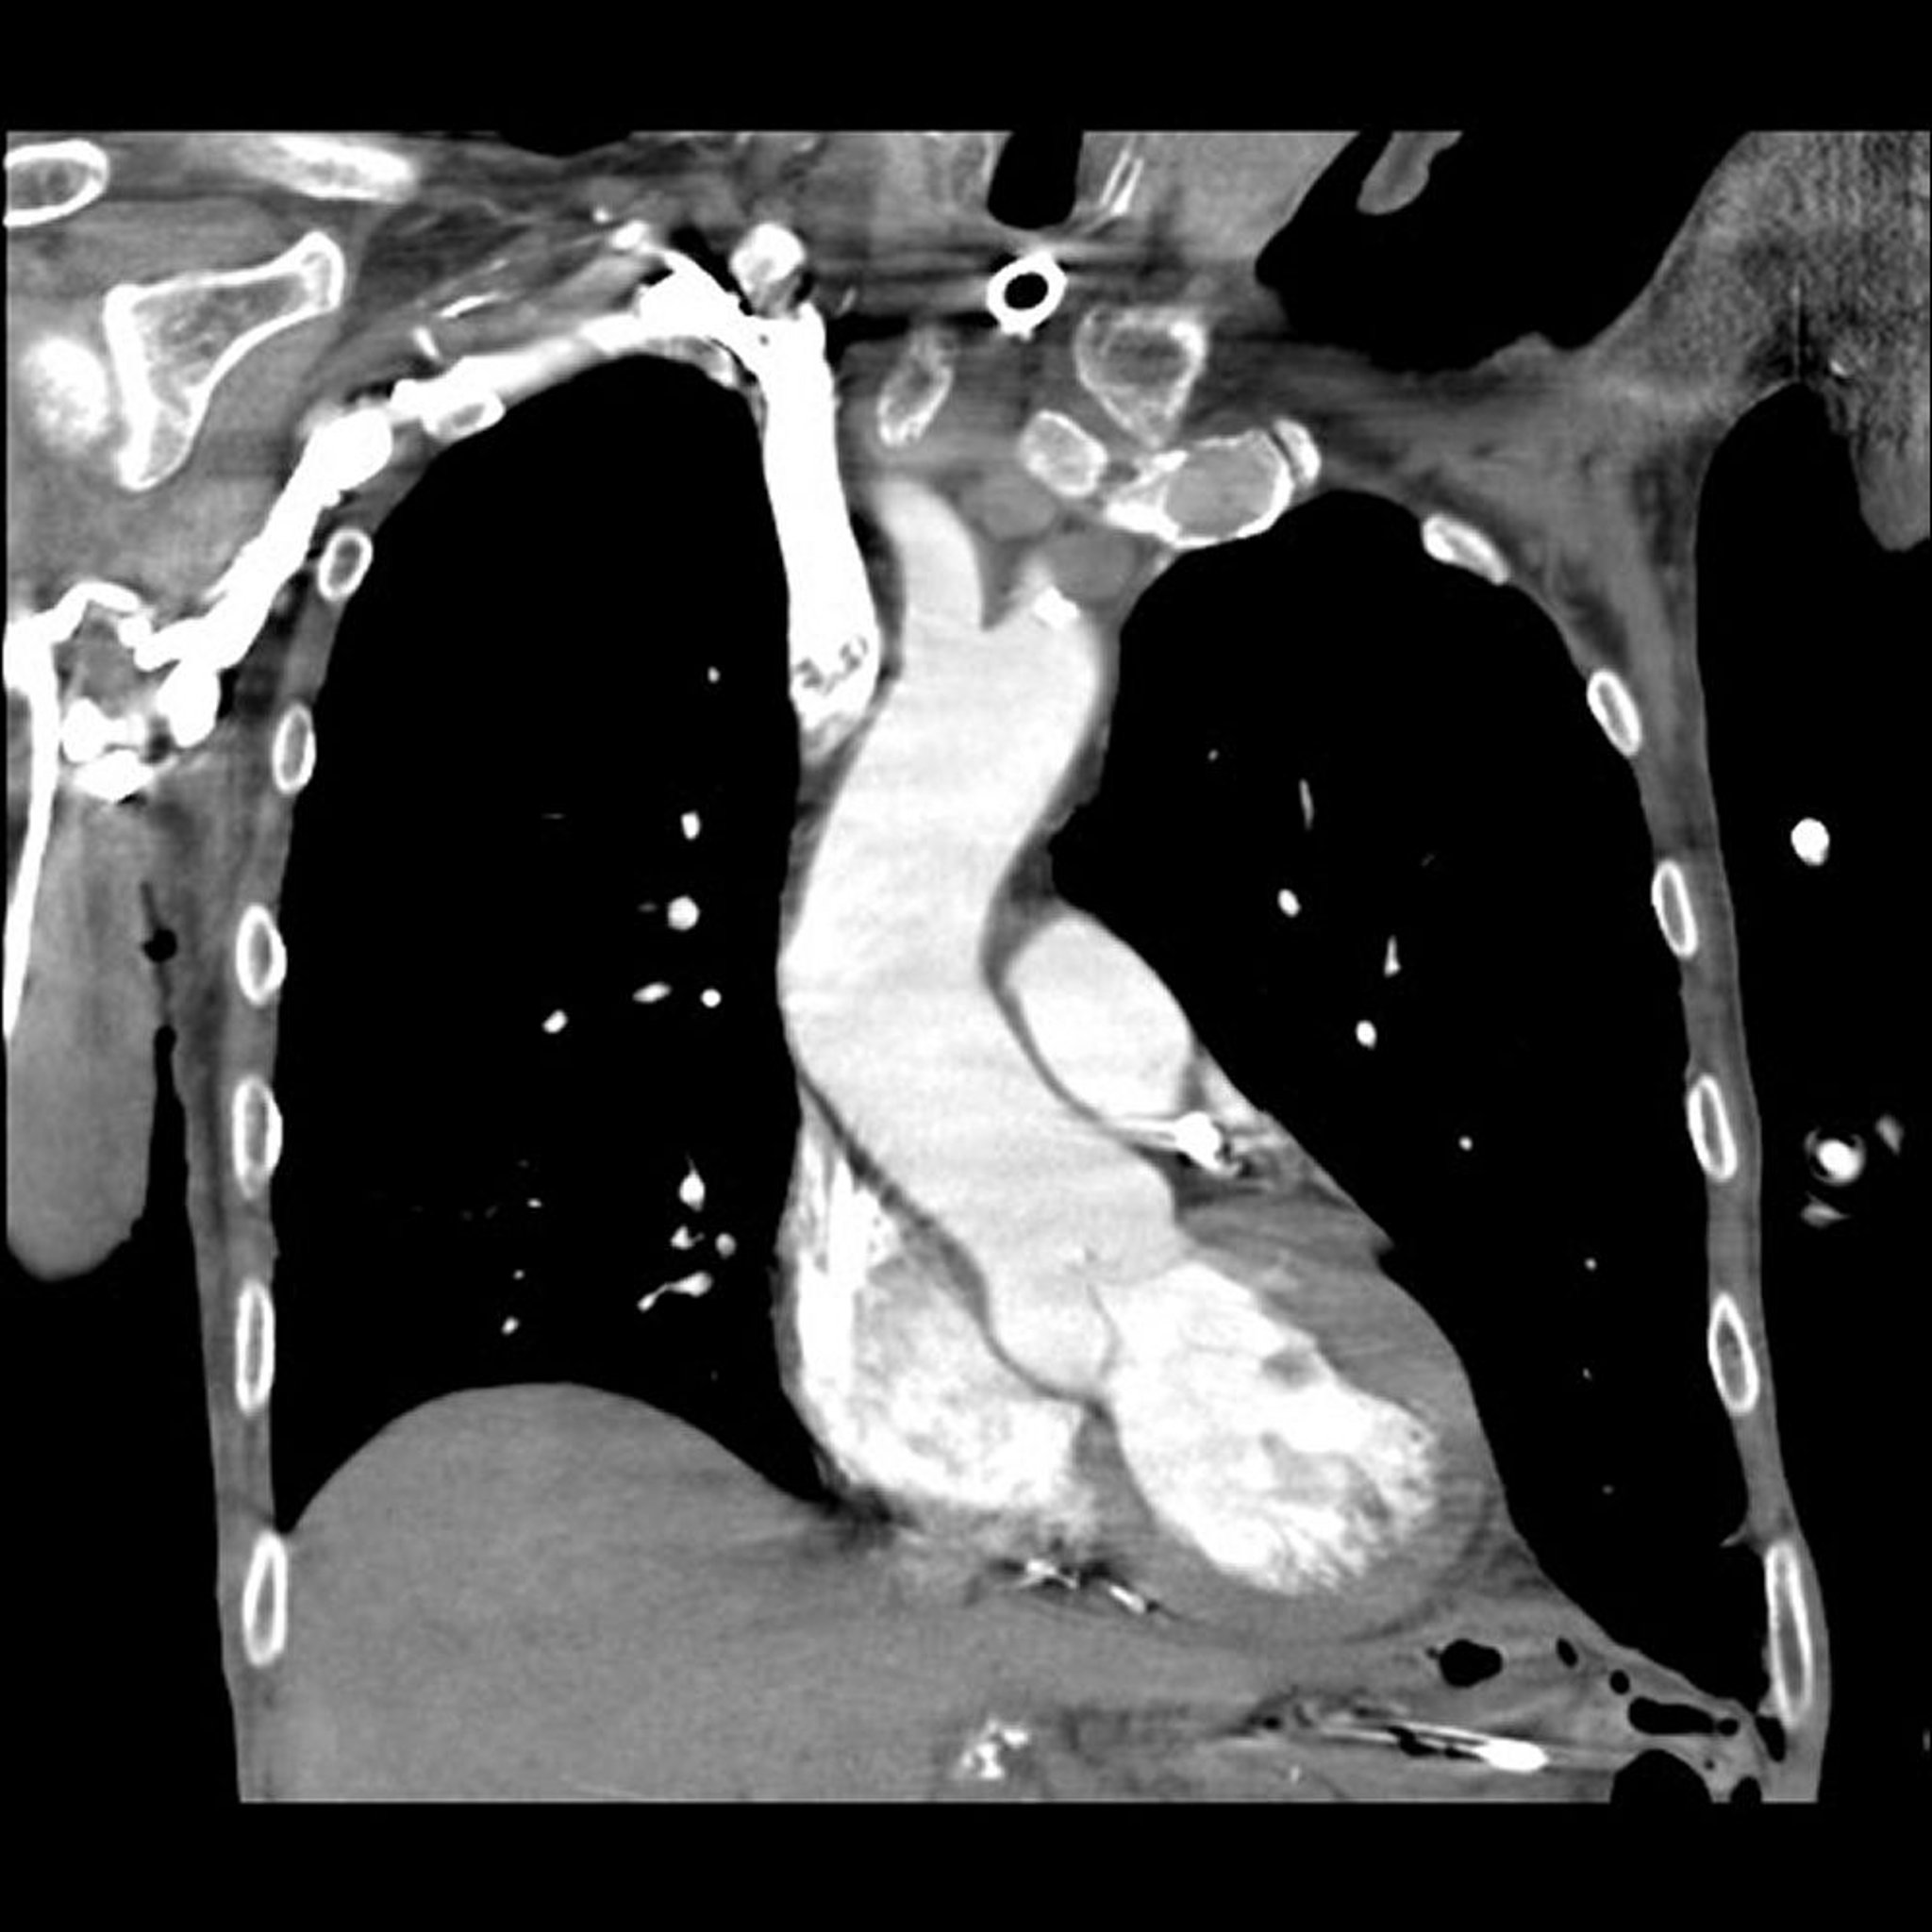

Computertomografie (CT) und pulmonale Angiografie

Bild von Dr. Mehmet Kocak.